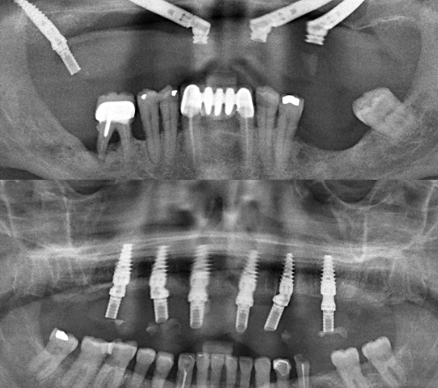

If you’ve recently had a tooth extraction—especially wisdom teeth—you might be worried about dry socket (also known as alveolar osteitis). This common but painful complication happens when the protective blood clot in the extraction site dislodges or dissolves too early, exposing bone and nerves. At Tribeca Dental Studio in NYC, we see patients every week […]...